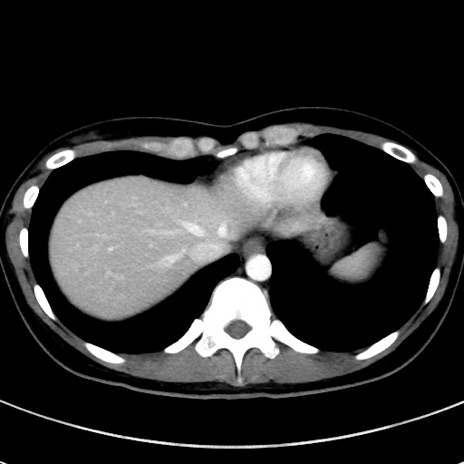

症例17(横断像)

【症例】20歳代女性

【主訴】嘔吐、下腹部痛

【現病歴】昨日夕食後に嘔吐し下腹部痛が出現。本日になっても嘔吐持続し改善しないため来院。

【身体所見】意識清明、BT 37.2℃、BP 108/67mmHg、腹部:平坦、やや硬、下腹部正中から右にかけて圧痛あり、反跳痛軽度あり、tapping pain(+)。

【データ】WBC 13600、CRP 14.94